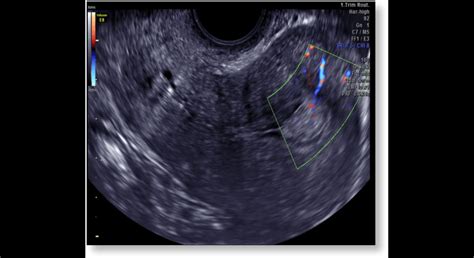

- Ultrazvuk (transvaginálny alebo brušný) - ultrazvukom sa vyšetrí maternica, vaječníky a vajíčkovody.

Liečba

Pre mamičku tešiacu sa na príchod bábätka nie je ľahké, ak sa vyskytnú nejaké komplikácie v rannom štádiu tehotenstva v podobe bolestí v podbrušku alebo krvavým výtokom. Je dôležité hneď o začínajúcich komplikáciách informovať svojho lekára, ísť na vyšetrenie, aby sa predišlo potratu, ak to je možné. Lekár vás vyšetrí s vaginálnym sonografom a určí, či je plod živý alebo odumrel v maternici.

Ako sa odhalí zamĺknutý potrat?

Ženy častokrát označujú oznámenie tejto smutnej udalosti za veľmi necitlivé zo strany lekára. Dozvedia sa len „surovú“ informáciu, že „tam nie je akcia“… V ranom štádiu tehotnosti je možné pomocou ultrazvukového vyšetrenia posudzovať prítomnosť aktivity základu srdcového svalu embrya. Limitácia tohto vyšetrenia sa posúva do nižších týždňov tehotnosti vďaka zdokonaľujúcej sa zobrazovacej technike najmä pri transvaginálnom vyšetrení. Napriek tomu sa v nízkych týždňoch tehotnosti všeobecne odporúča uvedené vyšetrenie aj niekoľkokrát opakovať, najlepšie s odstupom aspoň 48 hodín. Samozrejme podmienkou je nekomplikovaný priebeh. Ďalším faktorom je zastavenie vývoja embrya. Pokiaľ sa opakovaným ultrasonografickým vyšetrením preukáže neprítomnosť akcie srdca embrya a zastavenie jeho ďalšieho vývoja, musí vyšetrujúci lekár bohužiaľ konštatovať diagnózu zamĺknutého potratu. Uvedenú informáciu je nutné podať citlivo, s jasným vysvetlením stavu a ďalšieho postupu.